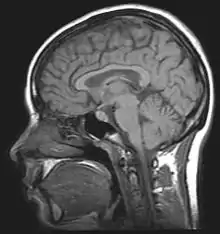

It is usually desirable to study memory in humans because we have the ability to subjectively describe experiences, and have the intellect to perform complex and indirect tests of memory. Lesion studies allow us to reduce the neural mechanisms of memory, and results from finely constructed psychological tests can help us make inferences about how memory works. Neuropsychologists attempt to show that specific behavioural deficits are associated with specific sites of brain damage. The famous case of HM, a man who had both his medial temporal lobes removed resulting in profound amnesia, illustrates how brain damage can tell us a lot about the inner workings of memory. One of the fundamental problems with studying human patients who have already acquired brain damage is the lack of experimental control.[1] Comparisons usually have to be made between individuals; exact lesion location and individual differences cannot be controlled for.

Cognitive neuroscience aims to reduce cognition to its neural basis using new technologies such as fMRI, repetitive transcranial magnetic stimulation (rTMS) and Magnetoencephalography (MEG) as well as older methods such as Positron emission tomography (PET) and Electroencephalography (EEG) studies. Due to the correlational designs used in fMRI, many scientists have coined this up and coming field as the new phrenology in the sense that techniques such as fMRI rely heavily on complex statistics.[17] Type 1 errors can lead scientists to draw premature and incorrect causal relationships if improper designs are used.[18]

A major complication that is raised in memory research is its fallible nature in humans. Having the ability to recall memories does not necessarily mean they are accurate. Our ability to store and process what is going on around us relies on memory being a constructive, fallible process. The technologies explained above may show areas of activation associated with certain behaviors, but without any idea of lesion location, it is difficult to pinpoint exactly what part of the brain relates to which behavioral deficits observed. Neuropsychologists have created various tasks designed to assess specific types of memory so that inferences about lesion location can be drawn from poor performances on these tests. Neuropsychological tests can aid us in understanding specific types of memory associated with specific sites of brain damage.